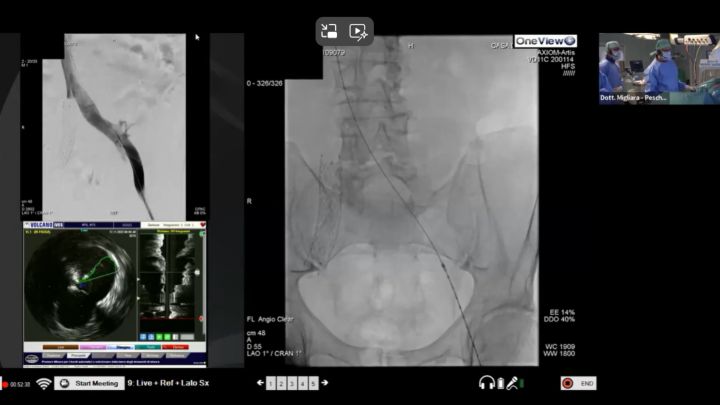

Видеозапись доклада, который представил 15.11.2024 доктор Правин Чандра (Dr. Praveen Chandra; г. Гургаон, Харьяна, Индия) при поддержке компании Philips в рамках XXVI Московского Международного конгресса по рентгенэндоваскулярной хирургии.

C использованием системы Volcano CORE Philips.